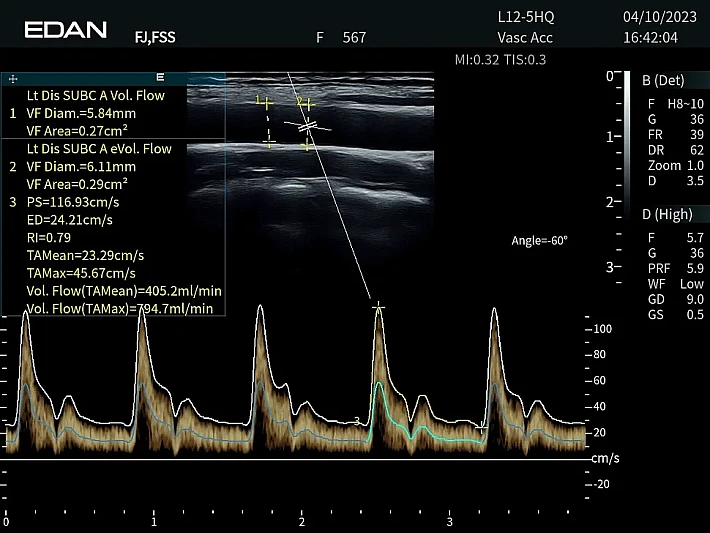

Медицинское оборудование и сервисное обслуживание